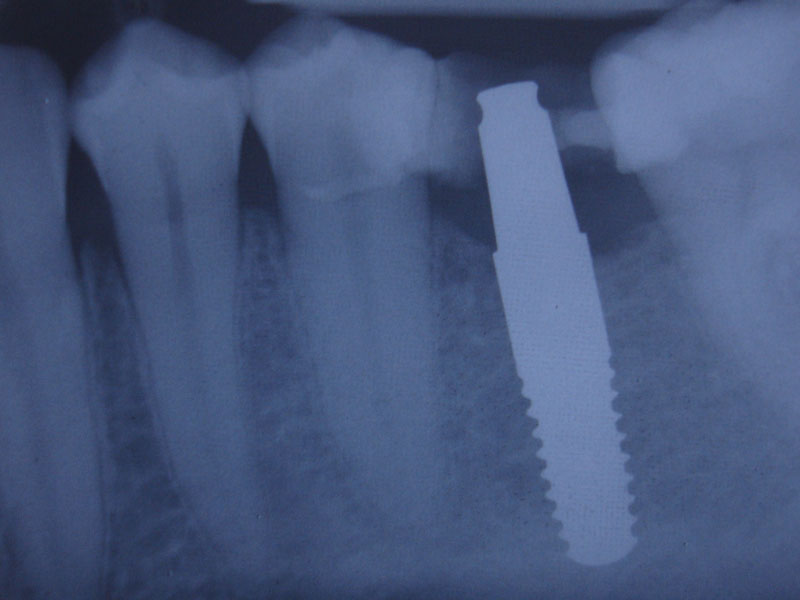

Folosim implanturi dentare WhiteSky si BlueSky, produse de firma Bredent, in Germania.

Implanturile dentare pot fi realizate din titan sau, mai nou, din zirconiu. Implanturile dentare din titan sunt implanturi folosite foarte des si care si-au dovedit rezistenta in timp.

Un rol important in tratamentul cu implanturi dentare il are calitatea acestora, din ce si cum sunt fabricate. Pentru fabricarea implanturilor dentare Firma Bredent foloseste Ti de grad 4, cel mai pur titan utilizat in medicina, fara alte metale, evitand astfel riscul aparitiei complicatiilor.

De asemenea titanul este dublu laminat la rece, procedeu prin care se obtine o rezistenta mecanica superioara altor implanturi dentare care folosesc aliaje ale titanului (grad 1, 2, 3, 5 etc). In timpul procesului de fabricatie o atentie deosebita este acordata indepartarii reziduurilor de orice fel (uleiuri, acizi, substante folosite in producerea oricarui tip de implant dentar). Toate elementele utilizate ulterior in tratamentul protetic pe implanturi dentare sunt de asemenea fabricate din titan de grad 4. Prin toate acestea, numarul esecurilor este redus la minim.

Bredent produce aceste implanturi dentare in Germania, respectand standardele de calitate din Germania.